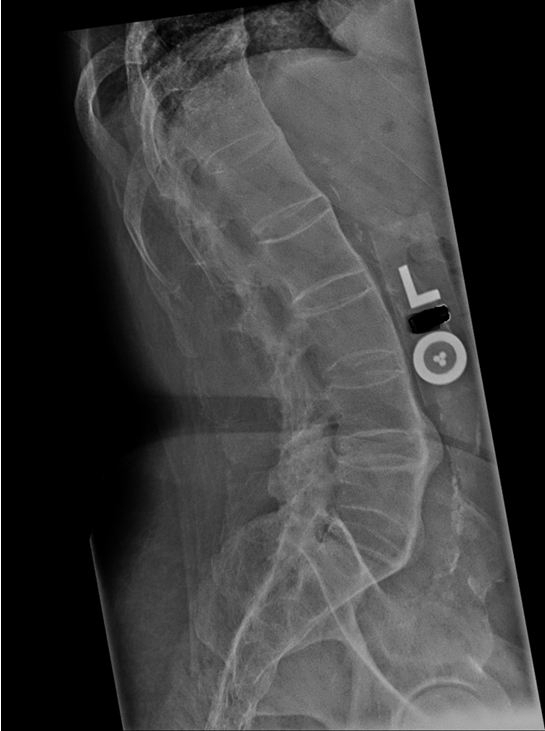

Ankylosing Spondylitis

Inflammatory back pain

Insidious onset at age less than 40 Symptoms >3 months Relieved with exercise but not rest Nocturnal pain

Examination findings

Arthritis (sacroiliitis) Reduced chest expansion & spinal mobility Enthesitis (tenderness at tendon insertion sites) Dactylitis (swelling of fingers & toes) Uveitis

Complications

Osteoporosis/vertebral fractures Aortic regurgitation Cauda equina

Laboratory

Elevated ESR & CRP HLA-B27 association

Imaging

X-ray of sacroiliac joints sMRI of sacroiliac joints

This patient has typical features of ankylosing spondylitis (AS), including chronic, progressive back pain and stiffness; pain relief with activity; lumbosacral tenderness; and reduced spinal range of motion. The incidence peaks in individuals age 20-30. Although AS has a male:female ratio of 2:1, it should be considered in any young patient with progressive low back pain and stiffness lasting >3 months.

In young patients with characteristic inflammatory back pain, plain x-rays of the pelvis showing sacroiliitis can confirm the diagnosis of AS. However, x-rays may be negative in early stages; MRI can confirm sacroiliitis in such cases. Fusion of the vertebral bodies with ossification of intervertebral discs (bamboo spine) also suggests the diagnosis. There is a strong association between HLA-B27 and AS, but whereas >90% of patients with AS have HLA-B27, only 5% of patients with HLA-B27 have AS. Therefore, HLA-B27 is not specific for AS and testing for it is not necessary for diagnosis. On the other hand, demonstrating radiographic changes of the axial skeleton is necessary for diagnosis.